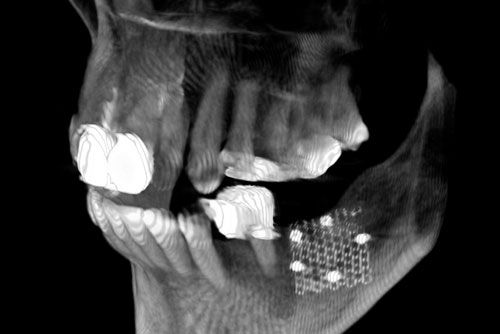

Normalerweise ist der Kieferknochen ein stabiles Fundament für Zähne. Gehen Zähne verloren, ist der menschliche Körper darauf ausgelegt, den Kieferknochen in dieser Region zurückzubilden. Dies wiederum kann den Einsatz von Implantaten erschweren. Die Lösung in diesen Fällen heißt Augmentation.

Augmentation bezeichnet die Vergrößerung bzw. Verbreiterung des Knochenlagers zur Aufnahme von Implantaten oder einfacher – die Regeneration von Kieferknochen. Dazu verwendet man entweder körpereigenen Knochen oder ein synthetisches Material. Eigenknochen-Transplantationen haben den Vorteil der unkomplizierten Einheilung, da Ihr Körper in diesen Fällen keine Abstoßungsreaktion zeigt. In unserer Praxis ist es möglich, Ihren eigenen Knochen mittels Ultraschalltechnik schonend zu verpflanzen.

Ist das gesamte Knochenangebot für eine Eigenknochenverpflanzung zu gering oder die Entnahme in individuellen Fällen zu riskant, so gibt es die Möglichkeit, synthetische Materialien einzusetzen. Dabei greifen wir ausschließlich auf zugelassene, in Deutschland oder der Schweiz produzierte und bewährte Produkte zurück. Die Behandlungsmethoden unserer Praxis sind streng nach dem Prinzip der Evidence Based Medicine (EBM) und den Leitlinien der Deutschen Gesellschaft für Implantologie (DGI) ausgerichtet.